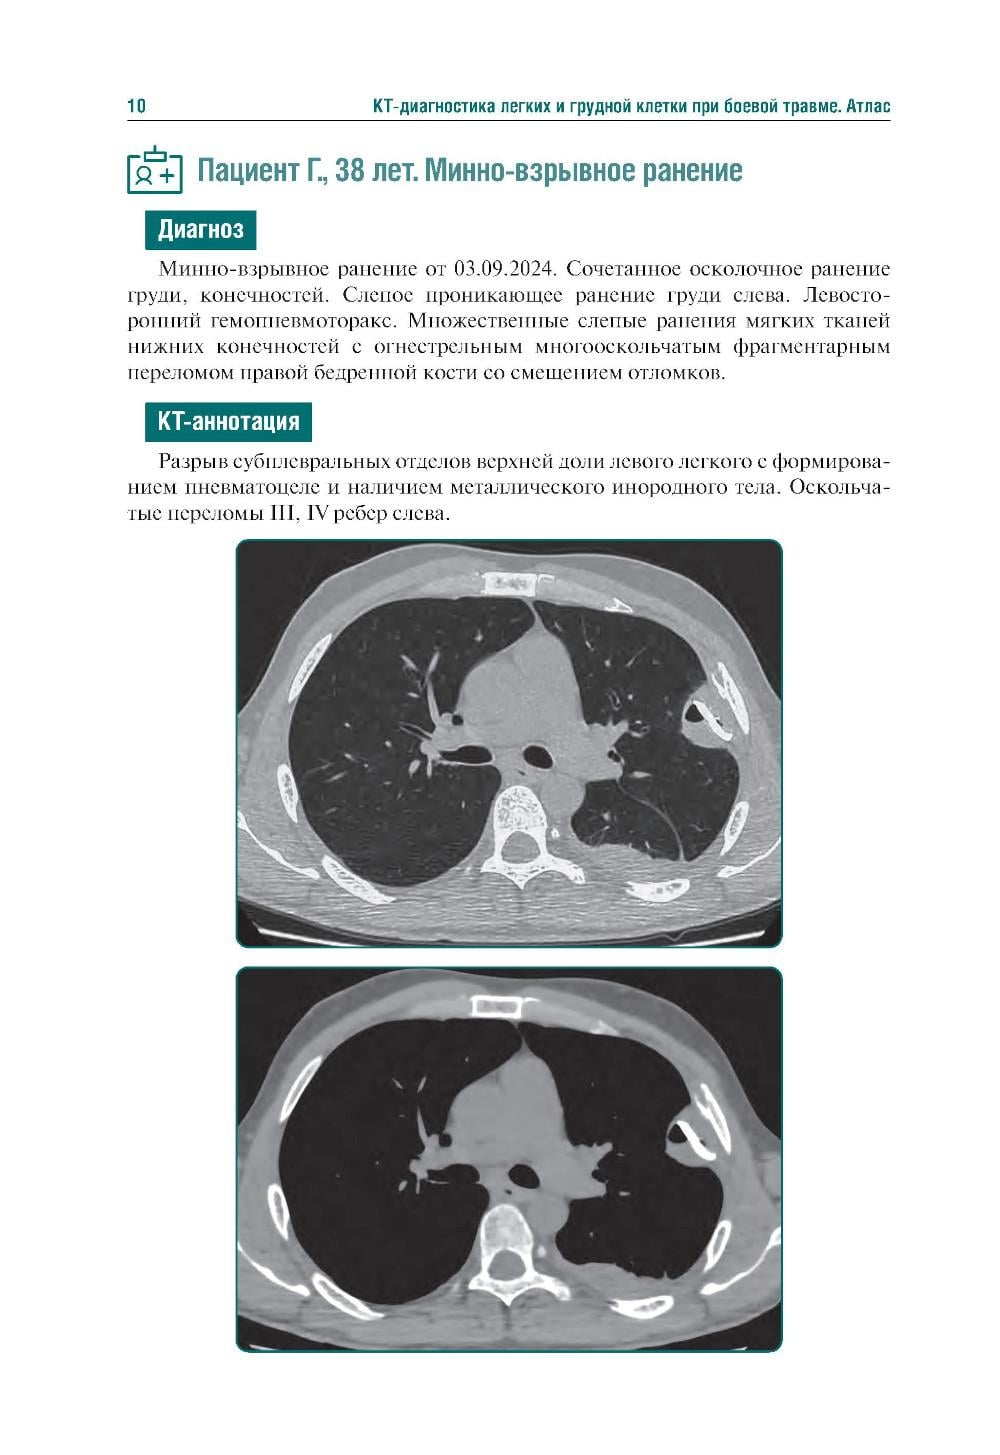

Издание представляет собой первый в Российской Федерации атлас, иллюстрирующий различные виды поражения легких, плевры и других структур грудной клетки у пациентов с боевыми ранениями. В современных условиях количество таких пациентов увеличивается, поэтому существенно возрастает значимость различных видов боевых травм, в том числе повреждений грудной клетки. В атласе представлены уникальные КТ-изображения различных видов боевой травмы грудной клетки, полученных в условиях современных вооруженных конфликтов. Помимо описания характера, условий получения травмы и выявленных повреждений, есть возможность просмотра изображений в формате DICOM. Атлас предназначен для врачей-рентгенологов, торакальных хирургов, пульмонологов, а также врачей других специальностей, занимающихся диагностикой и лечением пациентов с боевыми травмами.| Издательство | ГЭОТАР-Медиа |